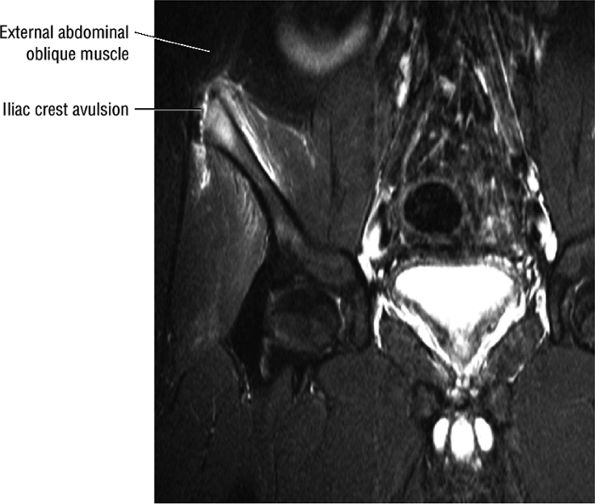

FIGURE 3.5 ● SARTORIUS The sartorius flexes and externally rotates the hip and flexes the leg on the thigh. The anterior superior iliac spine at the origin of the sartorius is a common location for an avulsion fracture. These injuries are usually seen in athletes (sprinters, jumpers, soccer players, and football players).

|